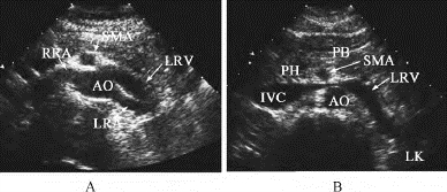

2.肾脏内部结构回声(图29-3) 肾实质周缘部分肾皮质呈均匀分布的点状低回声,强度低于肝组织回声,亦较脾组织回声为低。稍内层髓质,可见锥体呈三角形的更低回声区,呈弱回声,其底朝向肾皮质,尖朝向集合系统,并围绕于集合系统周围。

图29-3 正常肾脏声像图

左肾的冠状切面及横切面

肾盂、肾盏、肾窦脂肪组织等构成肾集合系统回声,呈成堆分布的高回声,位于肾的中央部分,占肾宽度的1/2~2/3,其分布范围与肾盂、肾盏相一致。